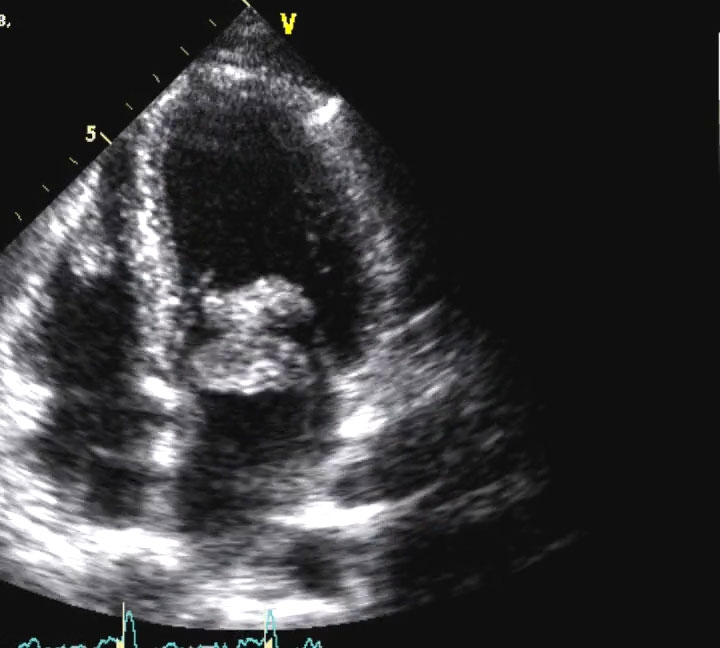

4 camere apicale COLOR. Evidente disfunzione sistolica con texture a "vetro smerigliato. Insufficienza mitralica e tricuspidale.